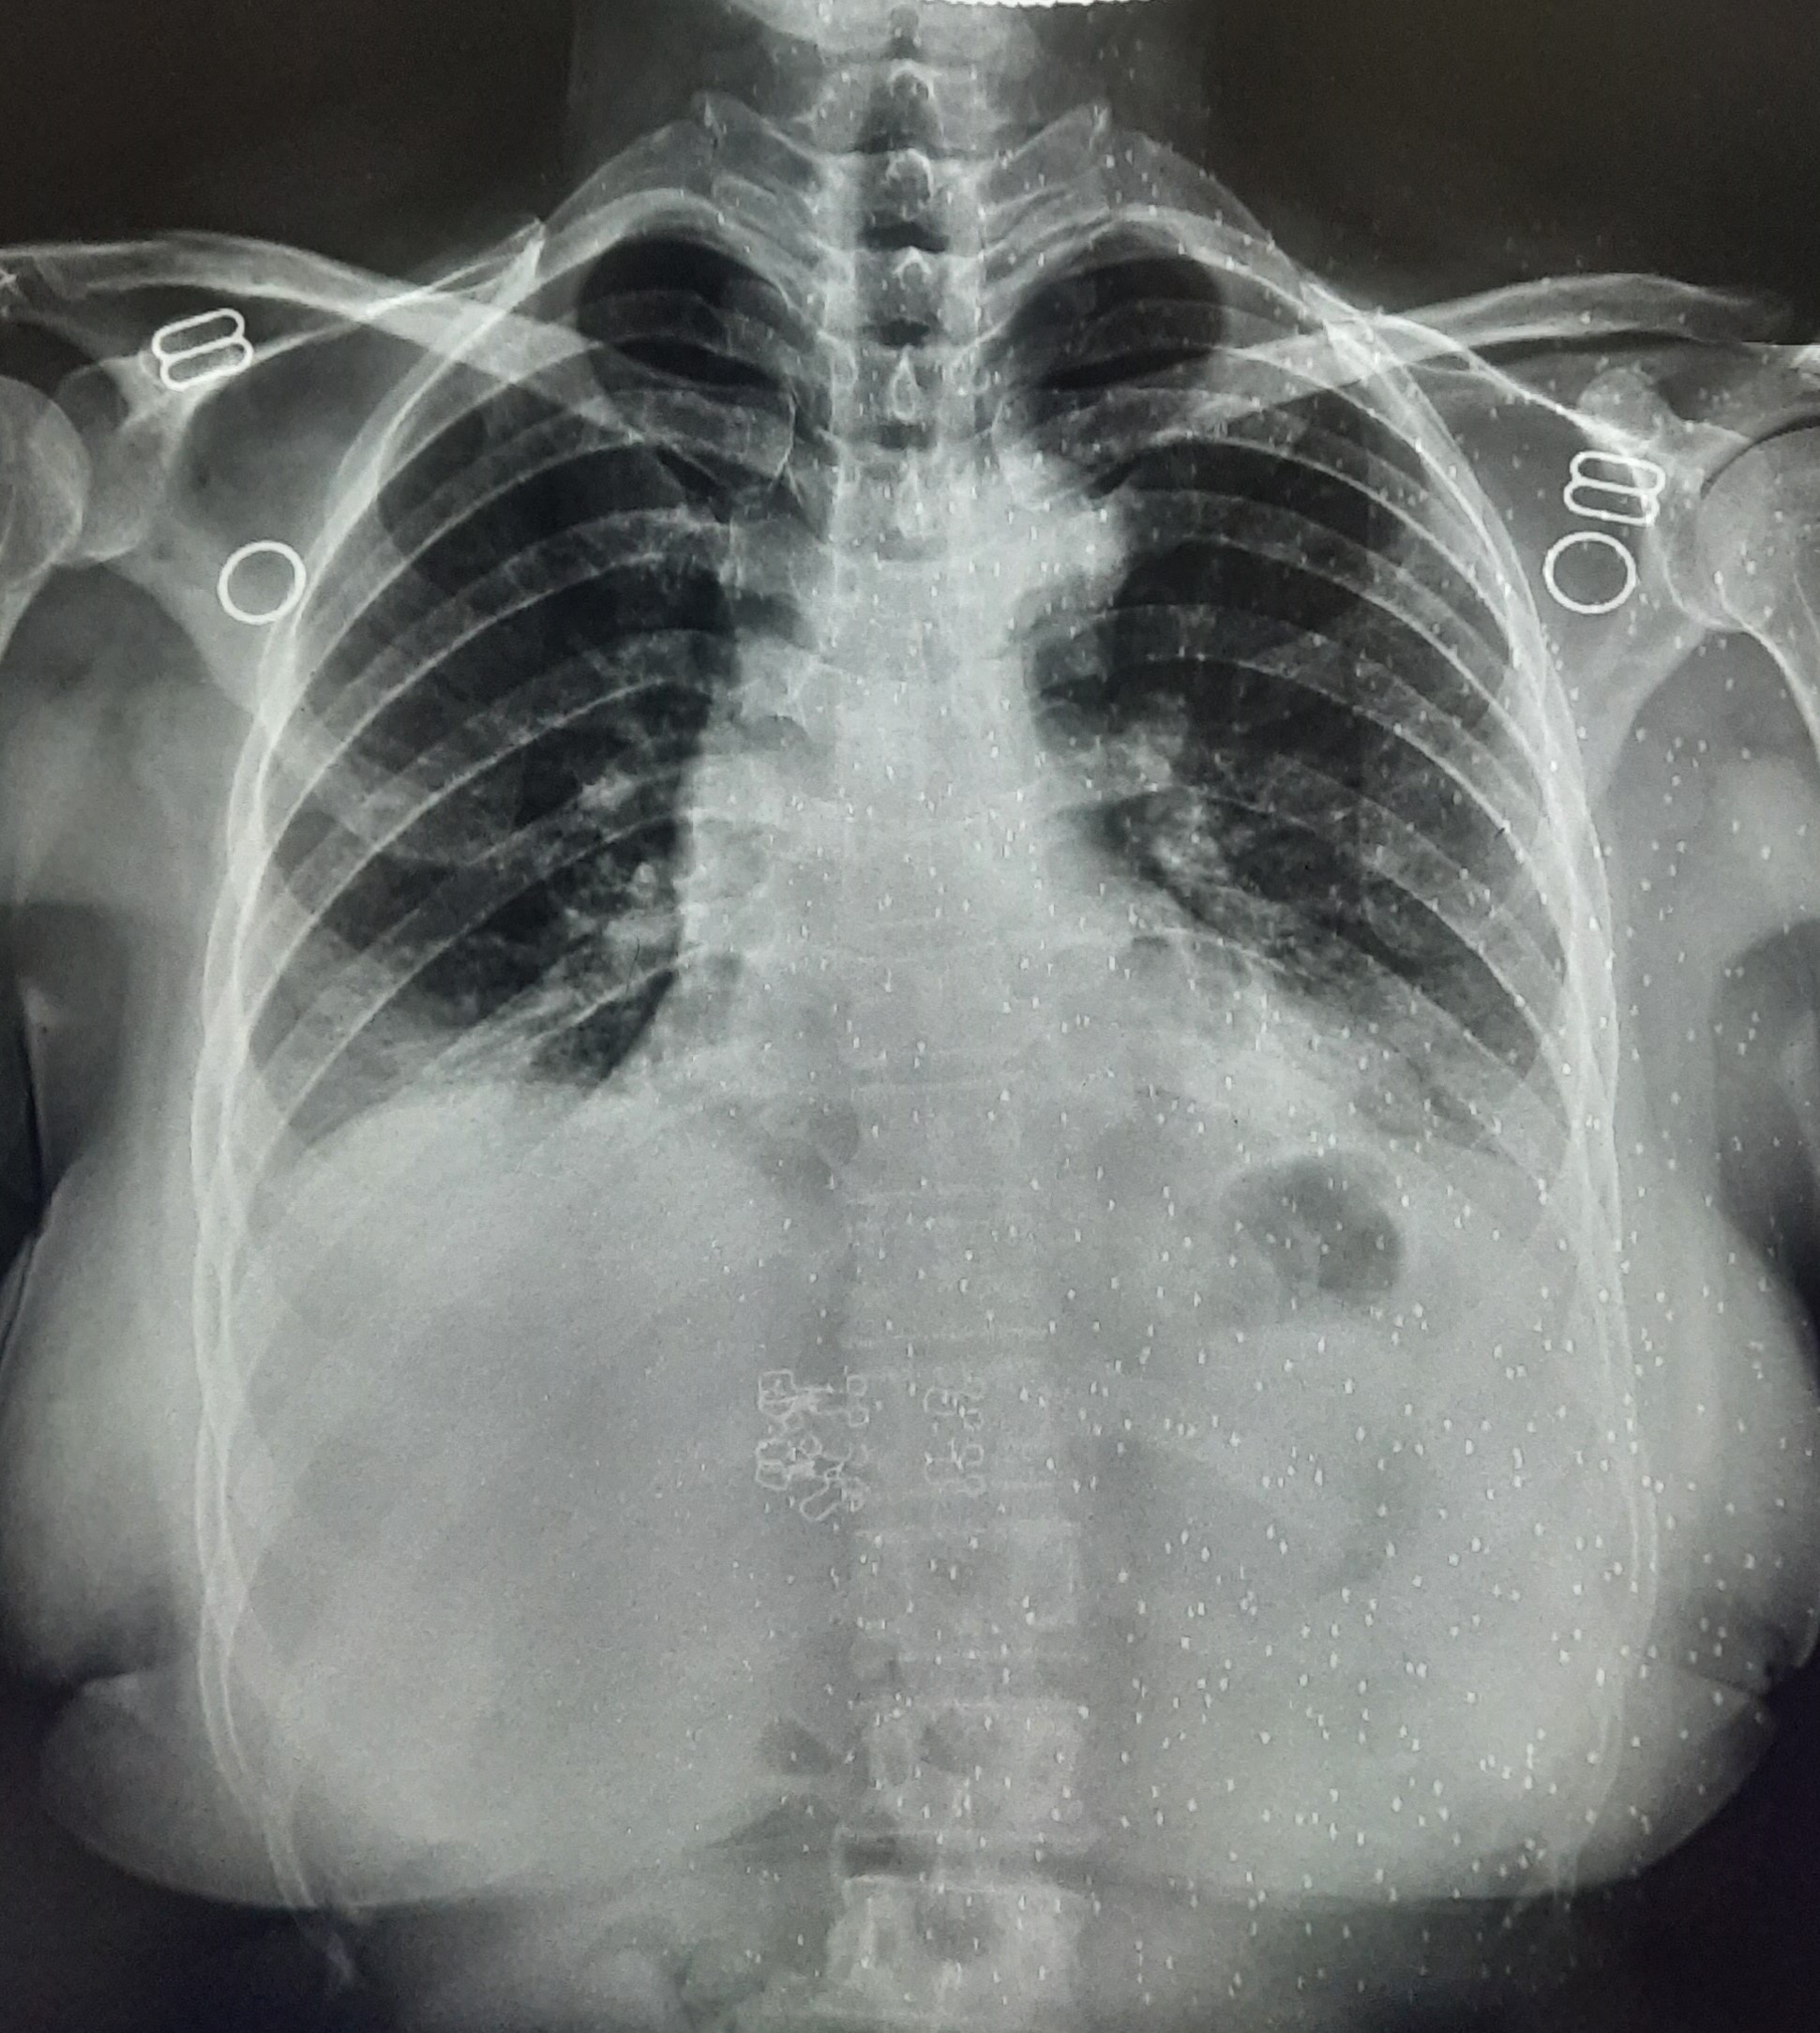

| 251 | IGGMC, Nagpur, Nagpur | P2 | 29-4221 | Ganpat Gaikawad | Consent taken on Paper | 70 Yrs. |

Provisional Diag : post TB sequele?

Final Diag : Fibrosis |

Non-TB Case (Confirmed) | Fibrosis | Abnormality visible on x-ray |